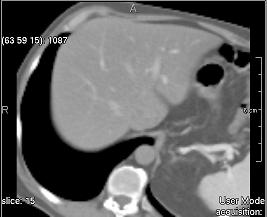

Contrast (simple)

../../../Modules/ML/MLFilter2/mhelp/Images/TextureFilterImages/contrast.jpg